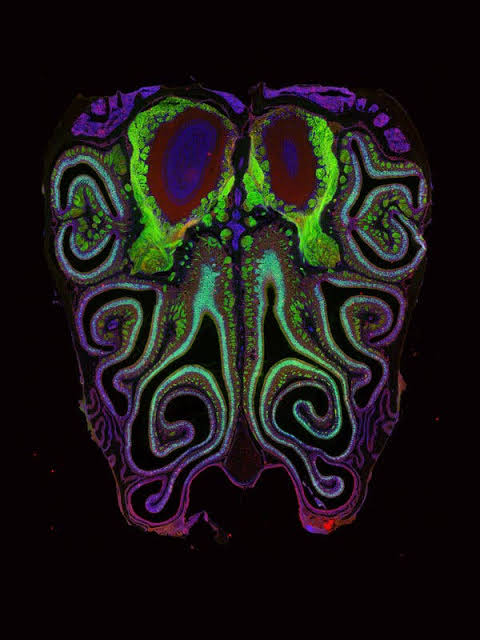

The odor receptors in the nose are not distributed at random but organized in a precise spatial pattern, two new studies reveal.